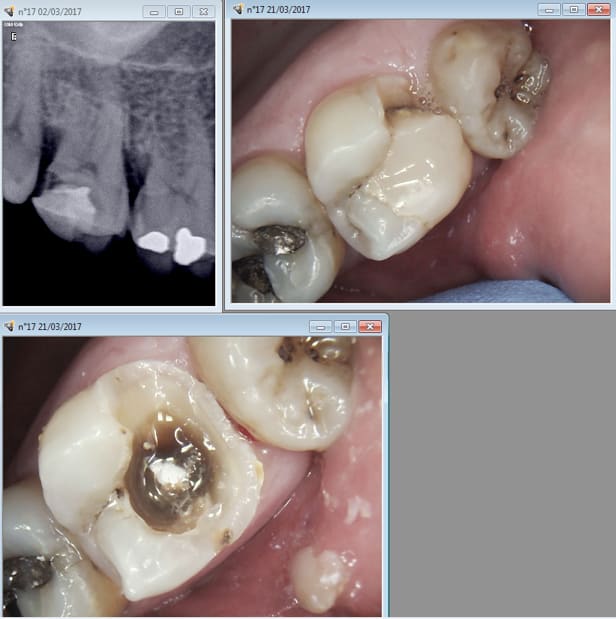

Bon je suis en soins là, on a zappé l'étape de l'onlay ( pas remboursé) et on va zapper l'étape du SC33 ( ceram pas assez remboursée). On est dans l'indication de l'ic coiffe ( ic super bien remboursé) . Ce qui me fait chier c'est que je vais encore ramer pour virer la reconstitution pré endo. -)

Je suis dans l'indication de l'onlay si j'estime que la pulpe n'est pas nase, je

suis dans l'indication de l'endo si j'estime le contraire. Enfin pour le SC33 ou

l'ic la décision se prend après préparation périphérique. Au vu de ces photos tu

en penses quoi ? Et encore la moitié qui reste c'est ma reconstitution pré

> endo. D'ailleurs il en reste un peu en distal après prépa de l'ic ca colle fort. . -)